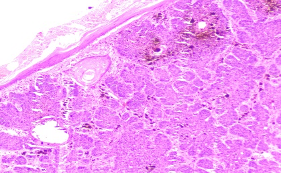

Section H and E x400. Mass in the wall of the small intestine in a 72 year old male patient who presented with frequent diarrhoea. Make you diagnosis.

Maltoma – small intestine- monocytoid B cells many showing plasmacytoid differentiation.

Patient had t(14;18)(q32;q21)